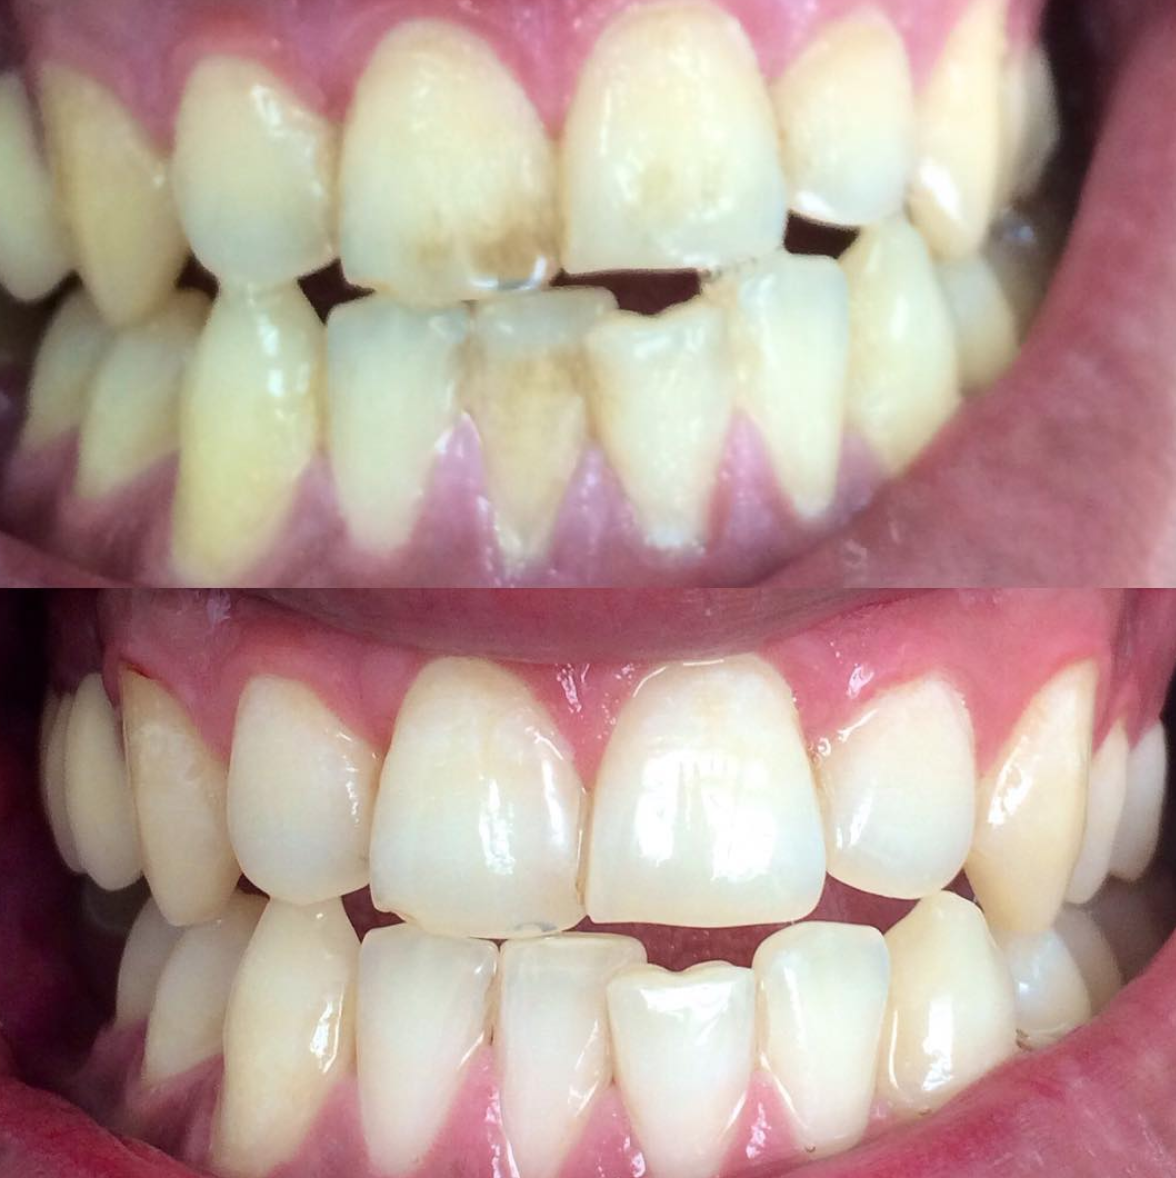

Обрести красивый естественный цвет зубов и гладкость эмали

Убрать с эмали налёт и зубной камень

Удалить пятна, появившиеся от пищевых красителей или вследствие вредных привычек

Удаление плотного налета, который образуется на зубах при плохой гигиене, вследствие курения или частого употребления чая или кофе проводится с помощью современной системы Air Flow. Специальный аппарат под давлением распыляет на зубы смесь воды и абразивных частиц. В наших клиниках используются самые щадящие порошки, чтобы не повредить поверхность эмали. Чистка Air Flow оказывает также осветляющий эффект — зубы становятся белее на один-два тона.